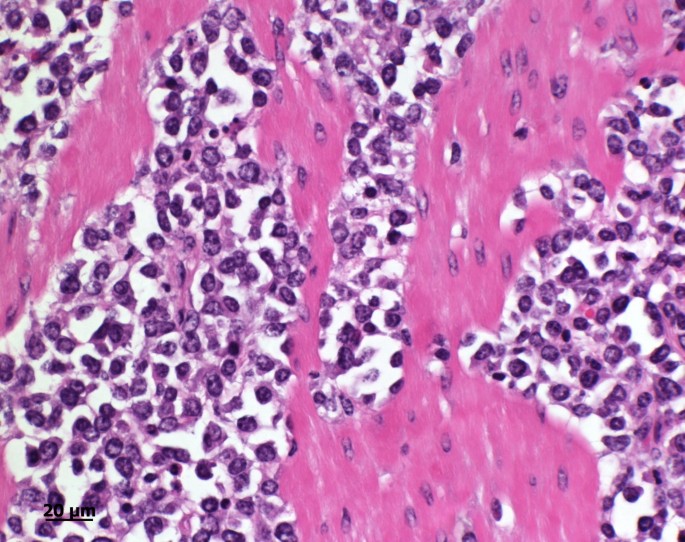

Микропрепараты: Лимфогранулематоз и Нодулярный Склероз

Раздел: Секреты мастерства